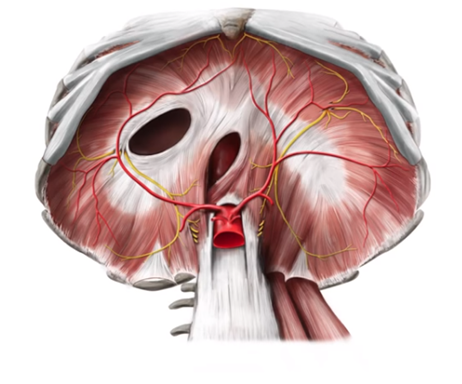

ANATOMİYASI

Diafraqma mərkəzi vətərdən, ətrafı isə eninəzolaqlı əzələdən ibarət olan yastı arakəsmədir. Formaca gümbəzə bənzəyən bu orqan qarın və döş boşluqları arasında yerləşir, öndə döş sümüyünə, arxada 1-3-cü bel fəqərələrinə, yanlarda isə qabırğa qövsünə birləşir. Diafraqmanın bel fəqərələrinə birləşən qalınlaşmış hissələri ayaqcıqlar adlanır.

Diafraqma yuxarıdan plevra ilə aşağıdan isə periton ilə örtülüdür.

Diafraqmada 3 böyük (aorta, ezofageal, aşağı boş vena) və kiçik 4 dəliklər mövcuddur. (parasternal – Morgan, Lorrey, plevroperotoneal - Bokdalek)

Qan təchizatı diafraqmal arteriya və venaları vasitəsi, innervasiyası isə diafrqamal sinirlərlə həyata keçirilir.

Şəkil 1. Diafraqmanın anatomiyası